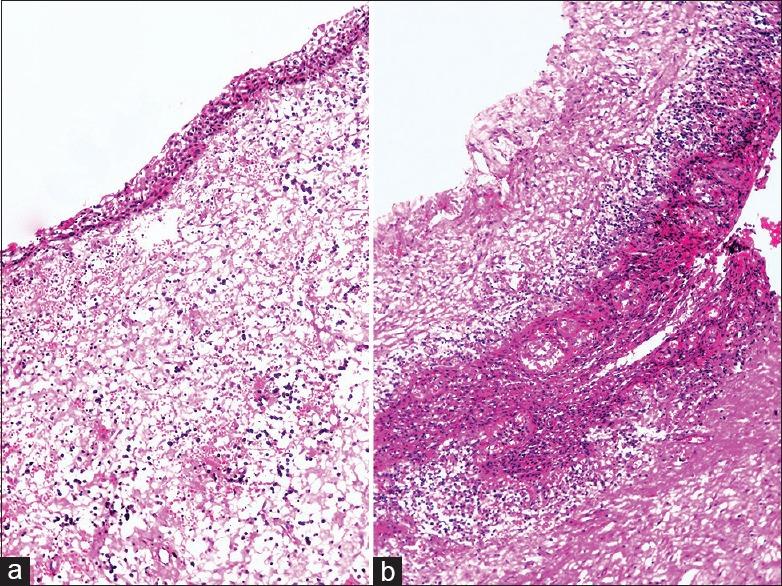

Dentigerous cysts are the most common developmental cysts of the jaws, accounting for approximately 20% of all jaw cysts. These cysts are usually unilateral, surrounding the crowns of impacted mandibular third molars. Bilateral dentigerous cysts have been associated with syndromes such as cleidocranial dysplasia and Maroteaux-Lamy syndrome. Nonsyndromic bilateral dentigerous cysts are extremely rare, particularly in the mixed dentition. Seventeen such cases have been reported till date. This article reports the eighteenth case of bilateral dentigerous cysts involving permanent maxillary canines in a 10-year-old boy.